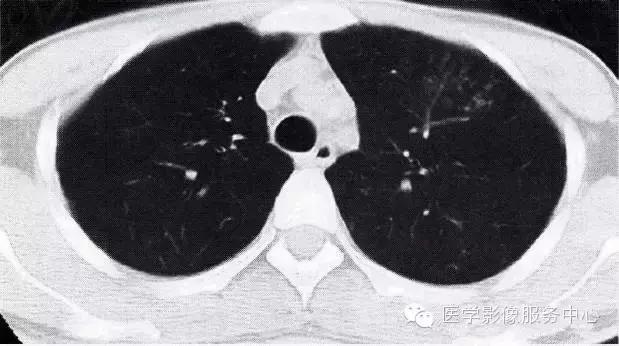

腺病毒肺炎如何判断呢?这一点需要借助腺病毒的病原学检测、肺部影像学检查,以及医生的经验来诊断,爸妈们可以做的,是在宝宝有如下疑似重症的表现时,尽快就诊: